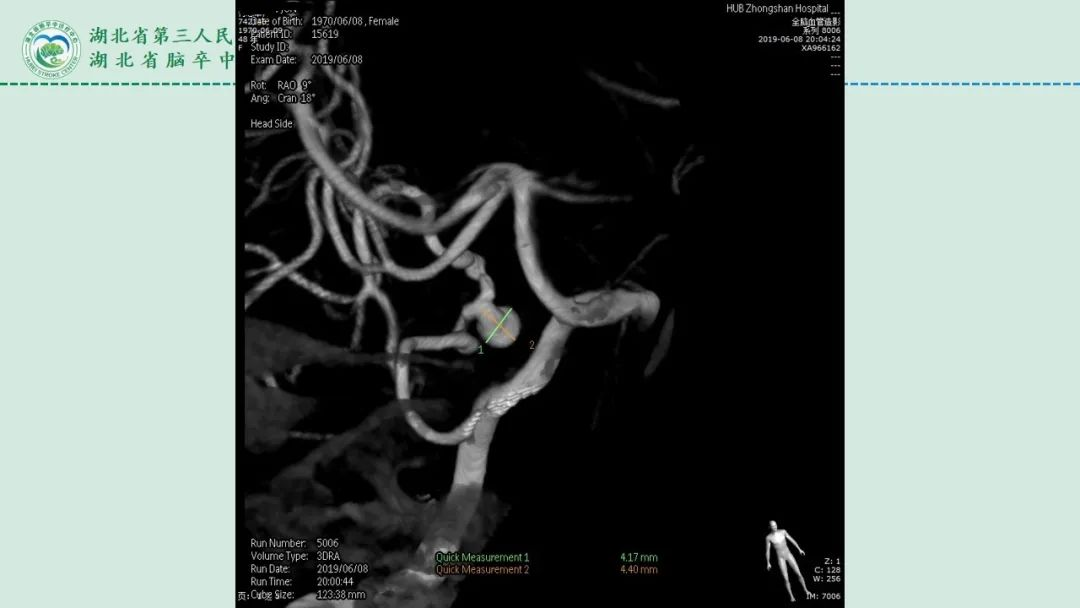

李俊教授团队:右侧PICA延髓扁桃体段多发动脉瘤

今日与大家分享的是《正海-妙术视界》第二百三十二期,由湖北省第三人民医院李俊教授团队带来的右侧PICA延髓扁桃体段多发动脉瘤,欢迎观看、分享。